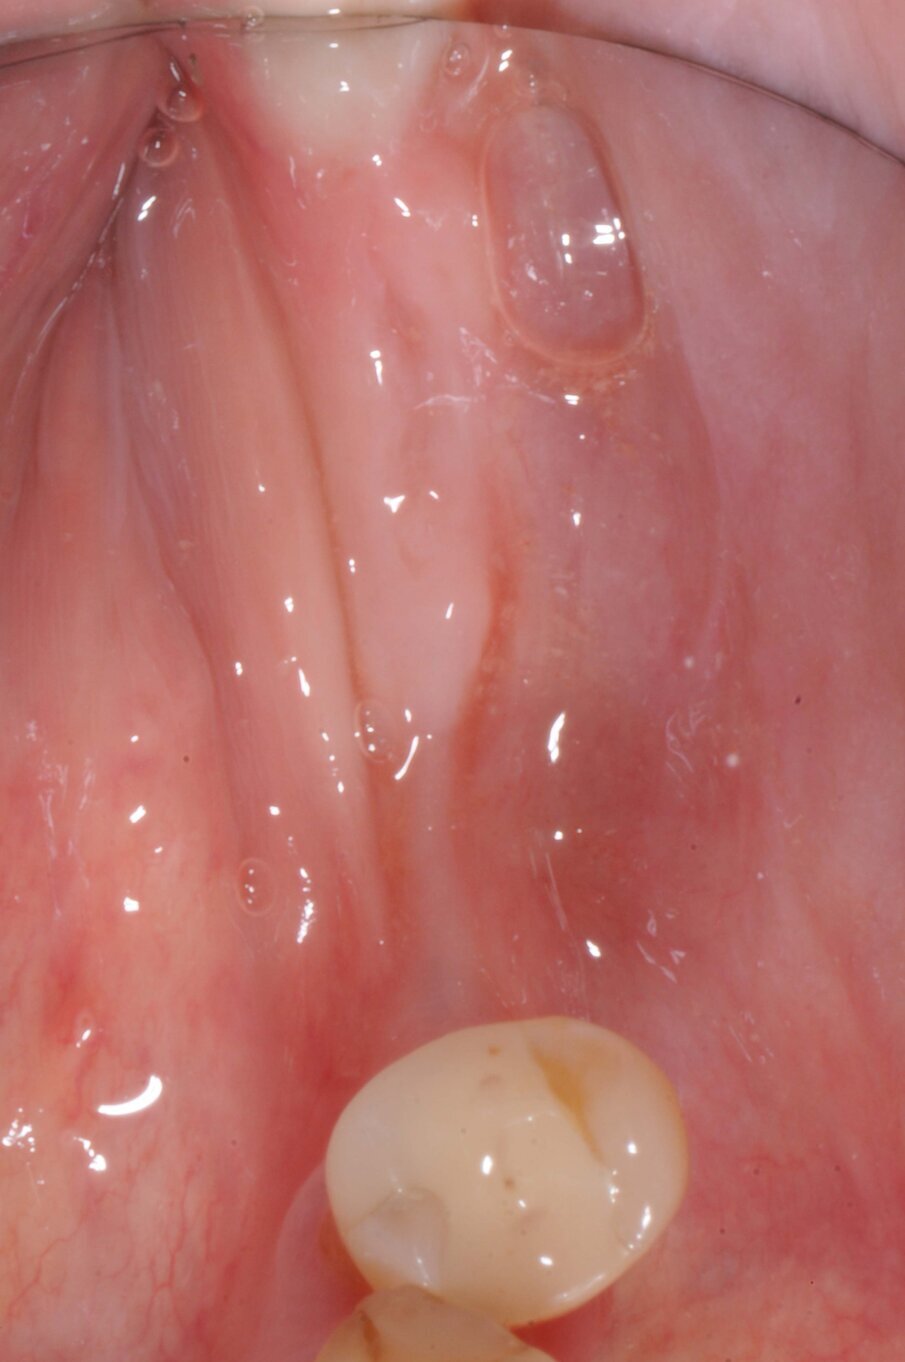

La paziente donna di 72 anni in buono stato di salute generale si presentò alla nostra attenzione per la mancanza dei denti nei settori inferiori posteriori (Fig. 1). Dalla radiografia OPT si notava che nel settore 4 era presente una zona di radiotrasparenza causata dalla recente perdita di due impianti dentali a causa di periimplantite. Si decise pertanto di iniziare a ripristinare il settore 3 (Fig. 2).

Dopo tre settimane i tessuti attorno agli impianti apparivano sani e privi di infiammazione. Era presente anche una banda di tessuto cheratinizzato. Fu presa un’impronta con tecnica del cucchiaio aperto e due settimane dopo furono consegnate due corone in zirconio avvitate. Il controllo radiografico evidenziava una buona stabilità dell’osso crestale (Figg. 10-13).